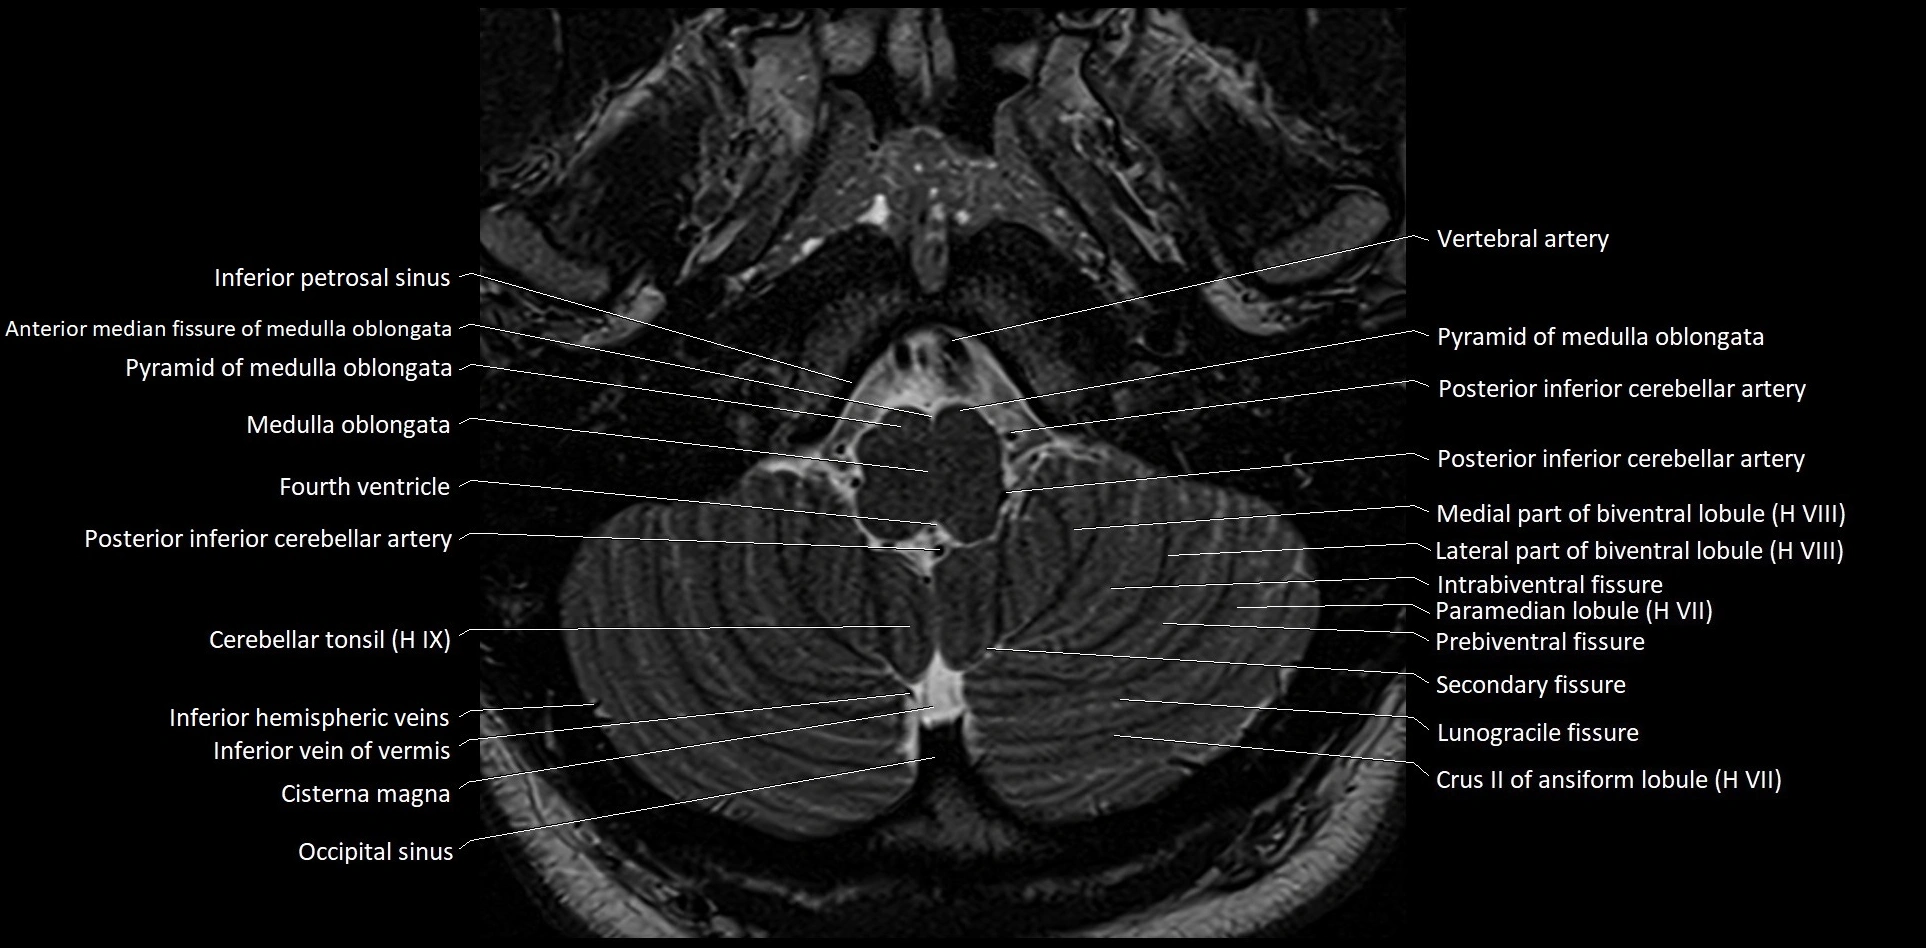

MRI images